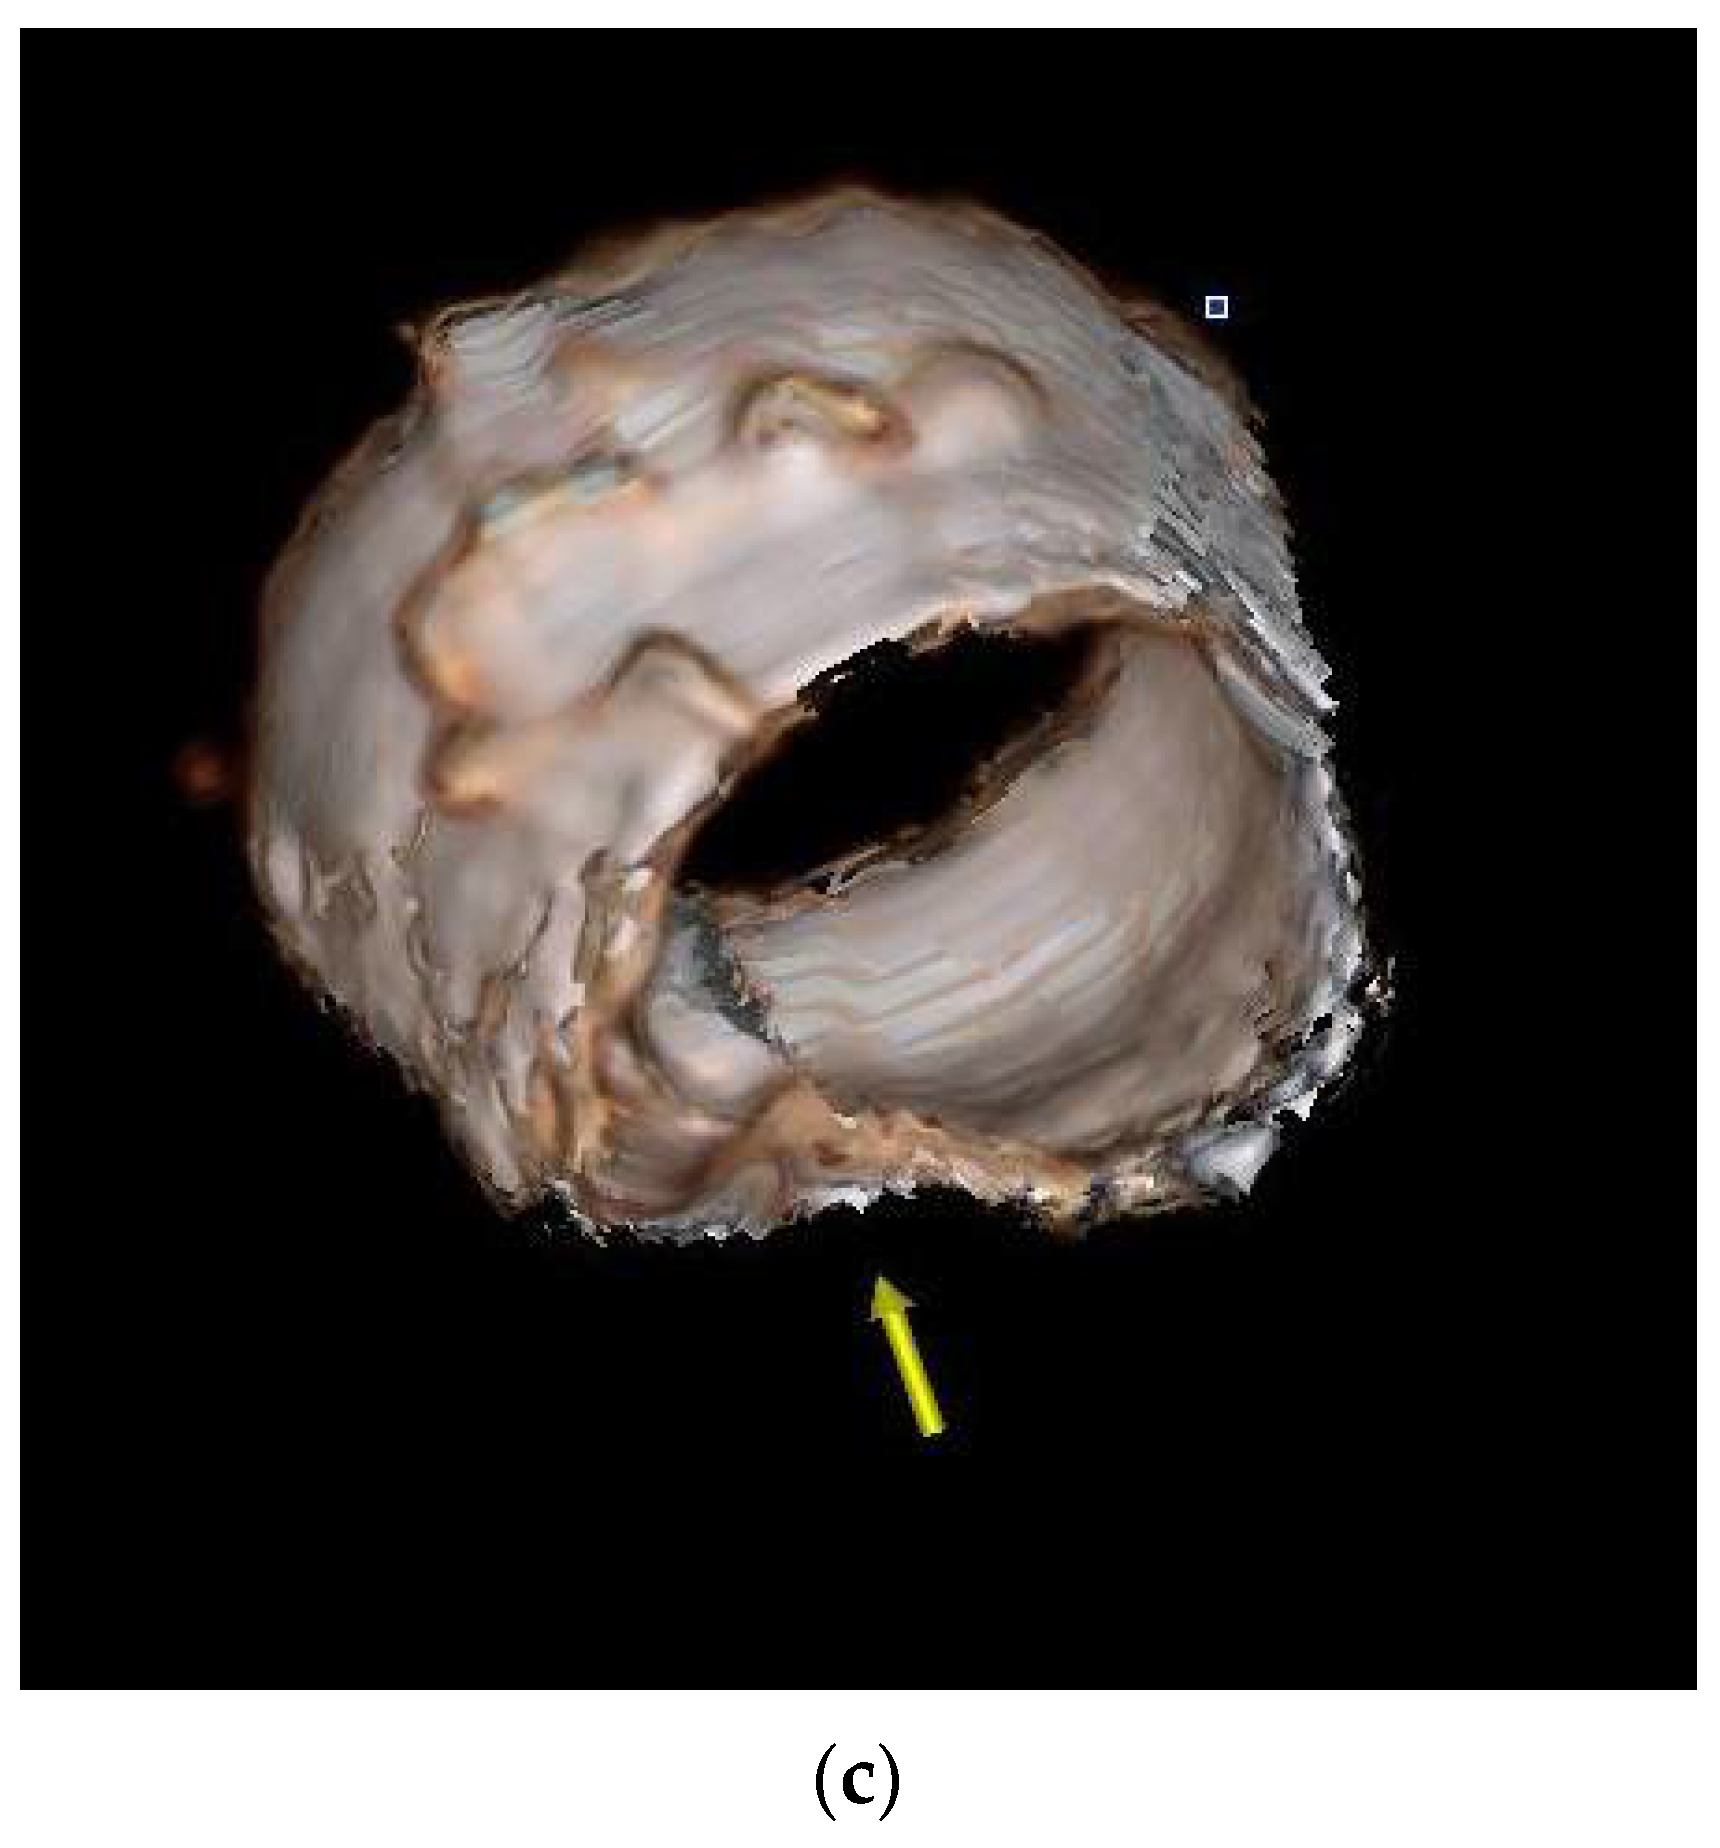

2.1. Case 1